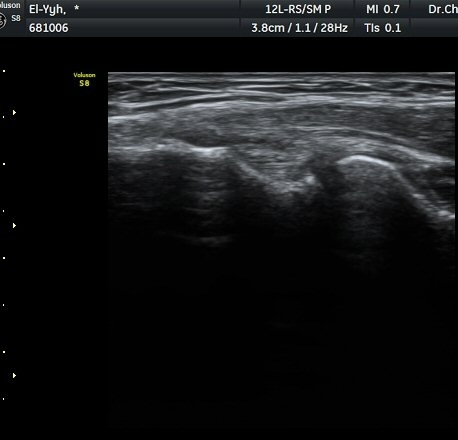

ÃÊÀ½ÆÄ °Ë»ç